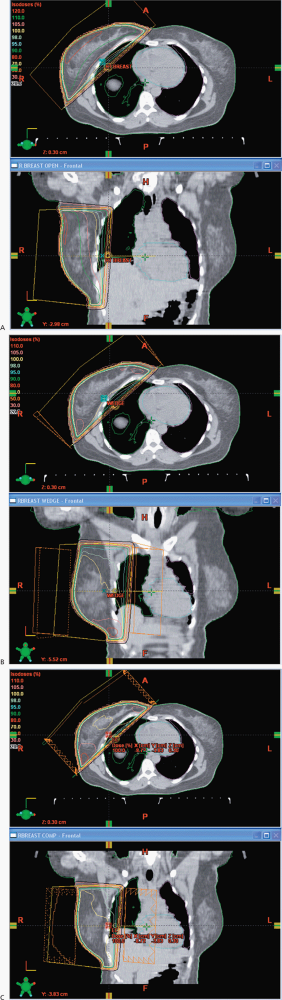

In this case, I would propose a boost of 10 Gy for a total dose of 60 Gy. The primary fields for the whole breast are opposed tangents with the patient on a breast board to obtain good geometry for breast coverage with the arms over the head in a supine position. We use a vac-loc to immobilize the head, arms and upper torso on the breast board with the board elevated to bring the mid sternum parallel to the couch and posterior collimator. We try to avoid, if possible collimator rotations to minimize beam divergence, and half beam block the deep portion of the tangent. The breast is outlined with wires placed at the superior, medial, inferior and lateral borders. The anatomic landmarks include the inferior margin of the head of the clavicle, mid sternum, 2 cm below the inframammary fold and the mid-axilla line. As all chest/breast setups are clinical, we do a control scan in the mid-region of the breast to identify the positioning and verify correctness of the lateral wire, which often requires some adjustment. This will minimize the setup uncertainty. The images are then sent to the treatment planning system for block design, with blocks placed to insure coverage of the breast tissue while minimizing the dose to the lung, heart, contralateral breast, and accounting for breathing motions. Some centers use deep inspiration breath hold technique, but this requires a fast scanner and rapid treatment administration. The boost field is generally given with electrons and if electrons are not suitable due to depth then a reduced opposed tangent field is useful. We do not treat the axilla.

The ACR categorization is consistent with my own recommendations: Treat the whole breast to 50 Gy at 2 Gy/fraction using opposed tangents then boost with a direct electron field an additional 5 fractions at 2 Gy/fraction to the lumpectomy cavity + 2 cm margin for a total dose of 60 Gy to the cavity.

A common approach is to treat to 50 Gy at 2 Gy per fraction generally with 6 MV opposed tangents and to boost the cavity to an additional dose of 10 Gy using either electrons or reduced tangents. I too feel that in many cases unless there is unusually high risk factors 16 Gy is higher than necessary. According to a recently published study from the University of Florence1, close margins of < 1 mm would warrant an increased boost dose to 16 Gy, if a re-excision was not attempted.

The whole breast should be treated to 50 Gy at 2 Gy/fraction. Alternatively, the breast has been treated to 46-50.4 Gy at 1.8 Gy/fraction. While there are studies that do not show benefit to boost, the ACR recommends a boost, although with a less score than for whole breast radiation. Most radiation oncologists recommend boost per the ACR appropriateness criteria, although they are somewhat wishy washy. Her risk factors are close margins, however, that has been cleared by the re-excision. The margins are negative. I would boost 10 Gy at 2 Gy/fraction to 60 Gy to the lumpectomy cavity.

She should receive radiation to the whole breast using opposed tangents, 6 MV, followed by a cavity boost to 60 Gy. The whole breast dose is 50 Gy at 2 Gy/fraction. The boost is reasonable in younger women with higher grade tumors.